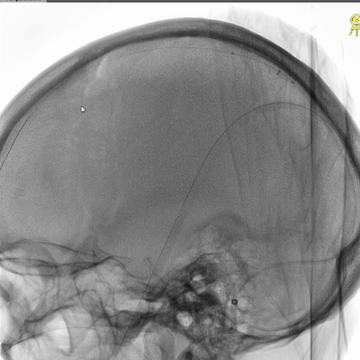

右侧股动脉穿刺置5F鞘,股动脉造影路图下穿刺右侧股静脉,置入8F鞘。6F长鞘(90cm,Cook)+6F中间管(115cm)+4F多功能管(125cm)组成同轴,泥鳅导丝导引下进入右侧颈内静脉颅底位置。泥鳅导丝超选进入右侧乙状窦和横窦,4F多功能管跟进乙状窦一段距离后难以继续前进,此时6F中间管在内衬4F管支撑下进入乙状窦,并前推进入横窦,成功建立治疗通道。

微导丝(Command 14)微导管配合,进入上矢状窦中部,交换出微导管,保留微导丝作为参照,引导后续微导丝微导管超选直窦。

微导管微导丝(Command 14)超选直窦成功后,交换出微导管。经微导丝送入3*30mm球囊,扩张直窦近段,并以BAT技术将6F中间管推送入直窦内,行血栓抽吸操作,吸出多量红色血栓。

中间管对直窦中远段抽吸后,送入微导丝,在微导丝保持通路情况下,中间管回撤抽吸直窦近段。

完成抽吸后,中间管和微导管直窦内造影均显示直窦管腔部分再通,恢复引流,但直窦近段存在狭窄。